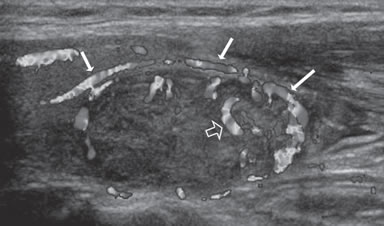

Figura 9. Cáncer papilar, de forma redondeada, de 30 mm de diámetro,

hipoecogénico, con microcalcificaciones periféricas y discontinuas

(flechas). En el aspecto posterior las microcalcificaciones

forman un contorno lineal (flecha abierta).

El patrón de calcificación periférica anular se consideró alguna vez que representaba un hallazgo benigno, pero un estudio demostró asociación con malignidad en 18,5% de los casos17. En ese estudio hubo una tendencia hacia un mayor riesgo de malignidad si el patrón periférico de calcificación era discontinuo (Figura 9) y un menor riesgo de malignidad si el patrón periférico de calcificación era liso y curvilíneo, en forma de cáscara de huevo (Figura 10).

De todos los signos ecográficos asociados a malignidad, las microcalcificaciones es el más específico (85-95%). La presencia de microcalcificaciones en un nódulo predominantemente sólido aumenta el riesgo de cáncer en tres veces y la presencia de calcificaciones gruesas aumenta el riesgo de cáncer en dos veces. El valor predictivo de las microcalcificaciones varía entre 42% a 94% y la sensibilidad entre 26% a 59%5.